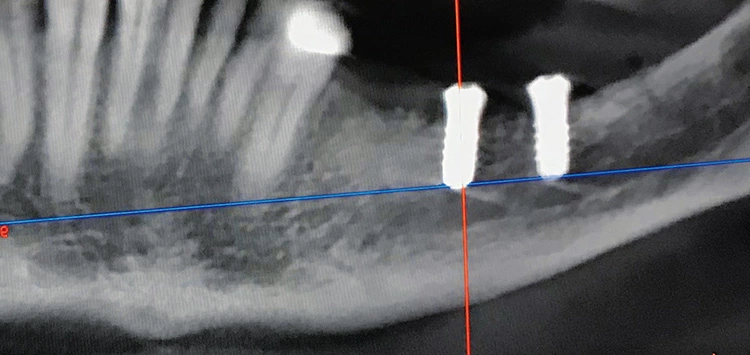

Bei der Vorstellung des Patienten zeigte sich ein qualitatives und quantitatives Knochen- und Weichgewebedefizit im linken Unterkiefer (34–37). Der Zahnverlust lag mehrere Jahre zurück und der Patient wünschte eine festsitzende Versorgung. In der radiologischen Diagnostik zeigte sich ein hochliegendes Foramen mentale.

Präoperativ wurde im Sinne eines Backward Planning erst die spätere Implantatposition und in Kenntnis dieser, die Ausdehnung des Titangitters festgelegt. Hierbei wurde festgestellt, dass sich zum einen das Foramen mentale direkt im Augmentations- und Implantationsbereich befindet und zum anderen der Verlauf des Nervus alveolaris inferior, trotz Augmentation, nur relativ kurze Implantate zulassen wird.

Bei der digitalen Planung des Gitters wurde dieser Aspekt besonders berücksichtigt und zudem auf die Lage des Foramen mentale speziell geachtet. Das Gitter wurde im Austrittsbereich ausgespart, um eine Traumatisierung zu vermeiden (Abb. 4-19).